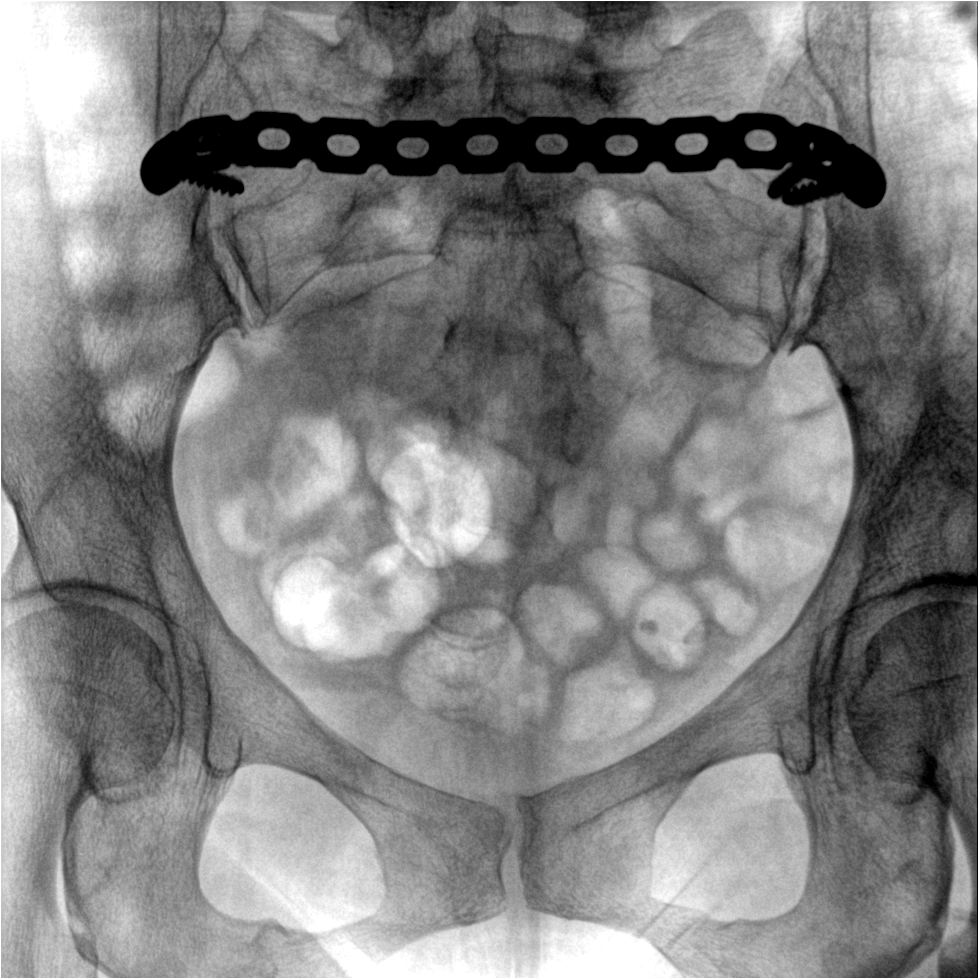

術(shù)中三維成像和橫斷面圖像提供多角度的手術(shù)診斷信息,輔助醫(yī)生進(jìn)行術(shù)中評估判斷,諸如骨折復(fù)位情況和內(nèi)植入螺釘?shù)某叽绾臀恢?,輔助手術(shù)更好地完成。

提供更大的術(shù)中三維成像視野,采集更多圖像信息,可一次拍全全段頸椎、全段腰椎、七節(jié)胸椎、雙側(cè)骶髂關(guān)節(jié)、股骨頭及單側(cè)盆骨。